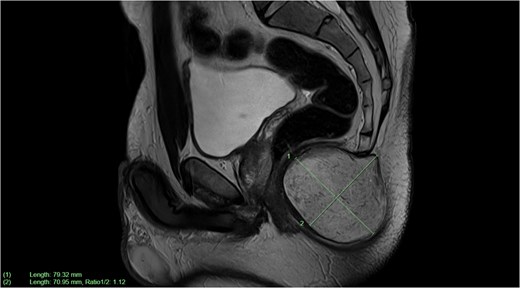

The GP had initially organized an ultrasound of the lesion, which was reported to have a solid hypoechoic inhomogeneous focus in the natal cleft. Subsequently, a CT pelvis scan showed a well-circumscribed low-density lesion at the distal coccyx. An MRI was then completed for surgical planning, showing a subcutaneous perineal mass causing elevation of the levator ani muscle and anterior indentation of the anal canal. There was no evidence of a fistula, abscess, infection, or an aggressive neoplastic process (Fig. 2). The initial preliminary diagnosis of this lesion was a tailgut cyst or EIC, and the patient was subsequently booked for an excision of said cyst.

Sagittal plane MRI image of large subcutaneous cystic structure compressing on the anal canal—measuring 7.9 × 7.1 cm in size.